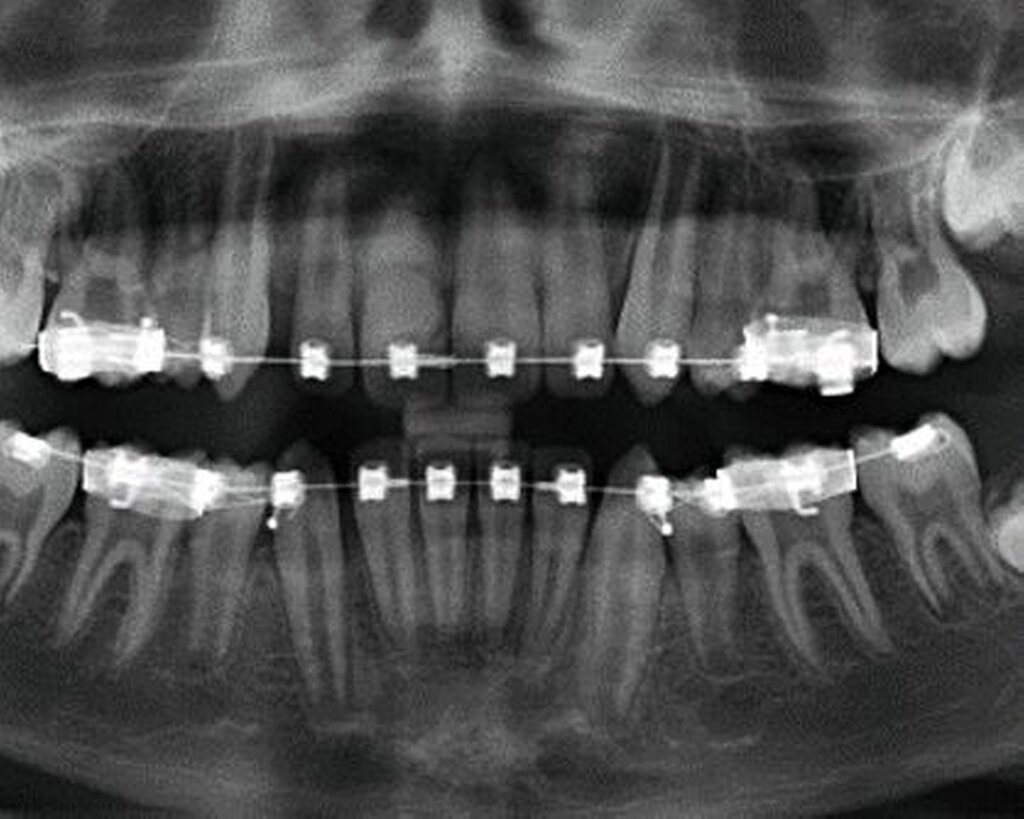

Nach der Einschätzung der Zellvitalität auf der oben genannten Basis folgt die therapeutische Intervention im Sinne der Replantation des betroffenen Zahnes in die gespülte Alveole (vorsichtige Entfernung des Blutkoagulums) mit steriler physiologischer Natriumchloridlösung. Schließlich muss die Replantation schonend erfolgen, da immer mit daran gedacht werden muss, dass es im Rahmen des Traumas zusätzlich zu einer Schädigung des Alveolarknochens gekommen sein kann (Abbildung 1). Diese Schädigung kann eine vollständige oder teilweise Alveolarfortsatzfraktur sein, die entsprechende Beachtung finden sollte. Im Anschluss erfolgt die Schienung des betroffenen Zahnes an den Nachbarzähnen. Dabei sollte ein Zeitraum von ein bis drei Wochen eingeplant werden (Tabelle 1).

Die Replantation sollte langsam und mit wenig Druck erfolgen, um eine zusätzliche Schädigung des Wurzelzements zu vermeiden. Anschließend sollte eine flexible Schienung des Zahnes erfolgen (Empfehlung 50) [Kahler et al., 2016].